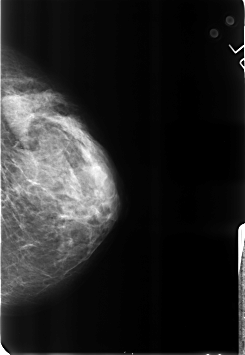

B_3184_1.RIGHT_CC

RIGHT_CC LINES 4536 PIXELS_PER_LINE 3120 BITS_PER_PIXEL 12 RESOLUTION 50 OVERLAY